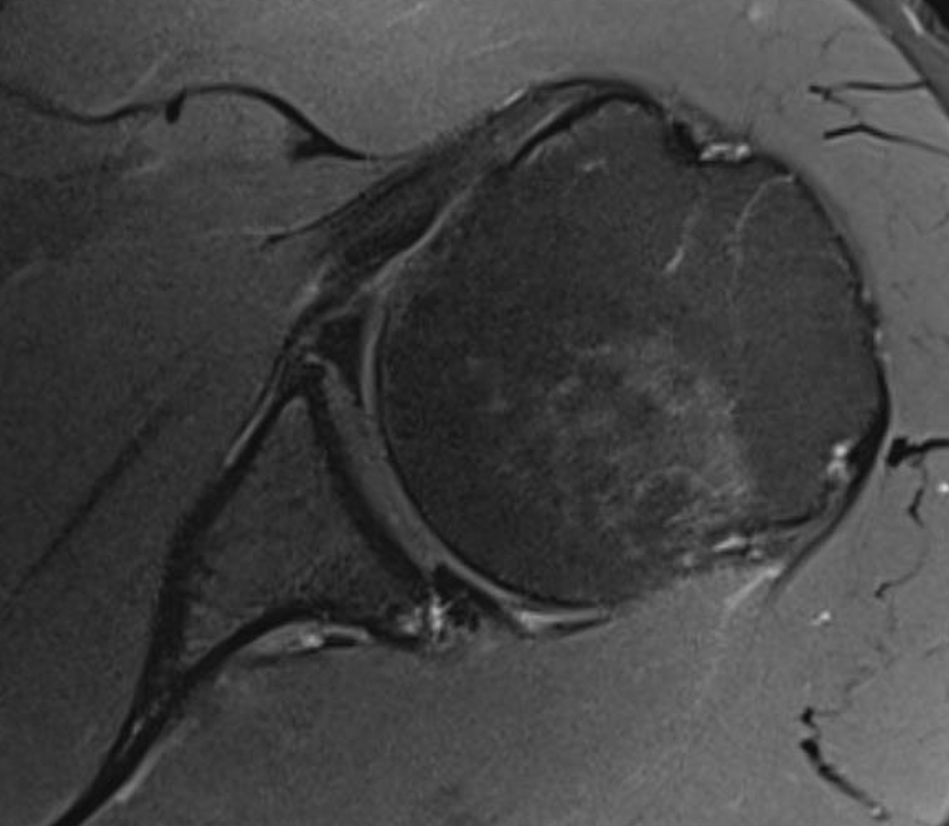

Posterior labral tear

Posterior labral tear

Kim lesion

- Kim lesion

- incomplete and concealed avulsion of the posteroinferior labrum

- superficial portion attached, deep portion detached

- labrum flat with loss of normal height resulting in retroversion of the chondrolabral glenoid